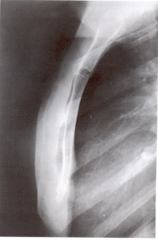

| Lateral Humerus | over rotation places the humeral head within the field of the chest |

| Lateral Humerus | epicondyles are not perpendicular humerus is internally rotated (lesser tubercle is in profile medially) overrotation |